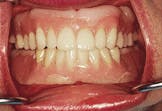

Figure 1-The patient has had four implants placed in the mandibular anterior segment. The denture is unsatisfactory to the patient in the three critical areas of esthetics, comfort and function.

Figure 1